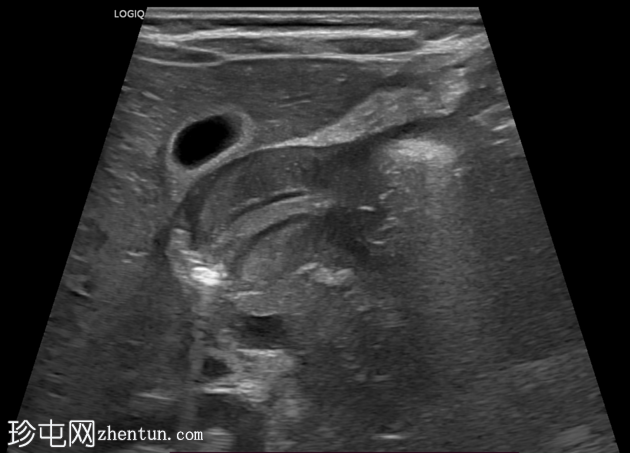

超声

检查

纵位

幽门管明显增厚,测量结果如下:

单层肌肉厚度约5毫米

管径约15毫米

管长约20毫米

横位图像显示幽门管狭窄的靶征。

总体测量结果提示肥厚性幽门狭窄。

病史和超声检查结果符合肥厚性幽门狭窄的特征。